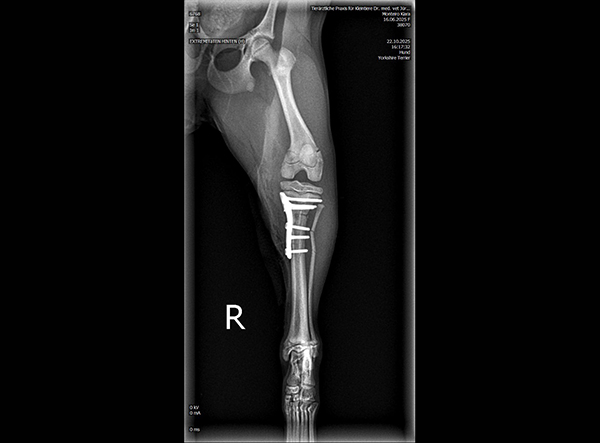

The patient, an 18-week-old female Yorkshire Terrier, was referred for surgery on October 21, 2025. The dog had sustained a fall from the owner’s arms, resulting in a fracture of the proximal tibial metaphysis just below the growth plate, along with a fibular fracture. Given the patient’s very small size and young age, precise anatomical fixation and minimal disruption of the growth zone were essential.

An open reduction and internal fixation (ORIF) was performed via a medial approach to the proximal tibia.Implant Used: 1.5 mm LeiLOX TPLO Swing Titanium Plate

The surgery was completed without complications. Postoperative radiographs confirmed anatomical alignment and stable fixation. With careful rehabilitation, the young Yorkshire Terrier is expected to regain full function and resume normal activity pain-free.